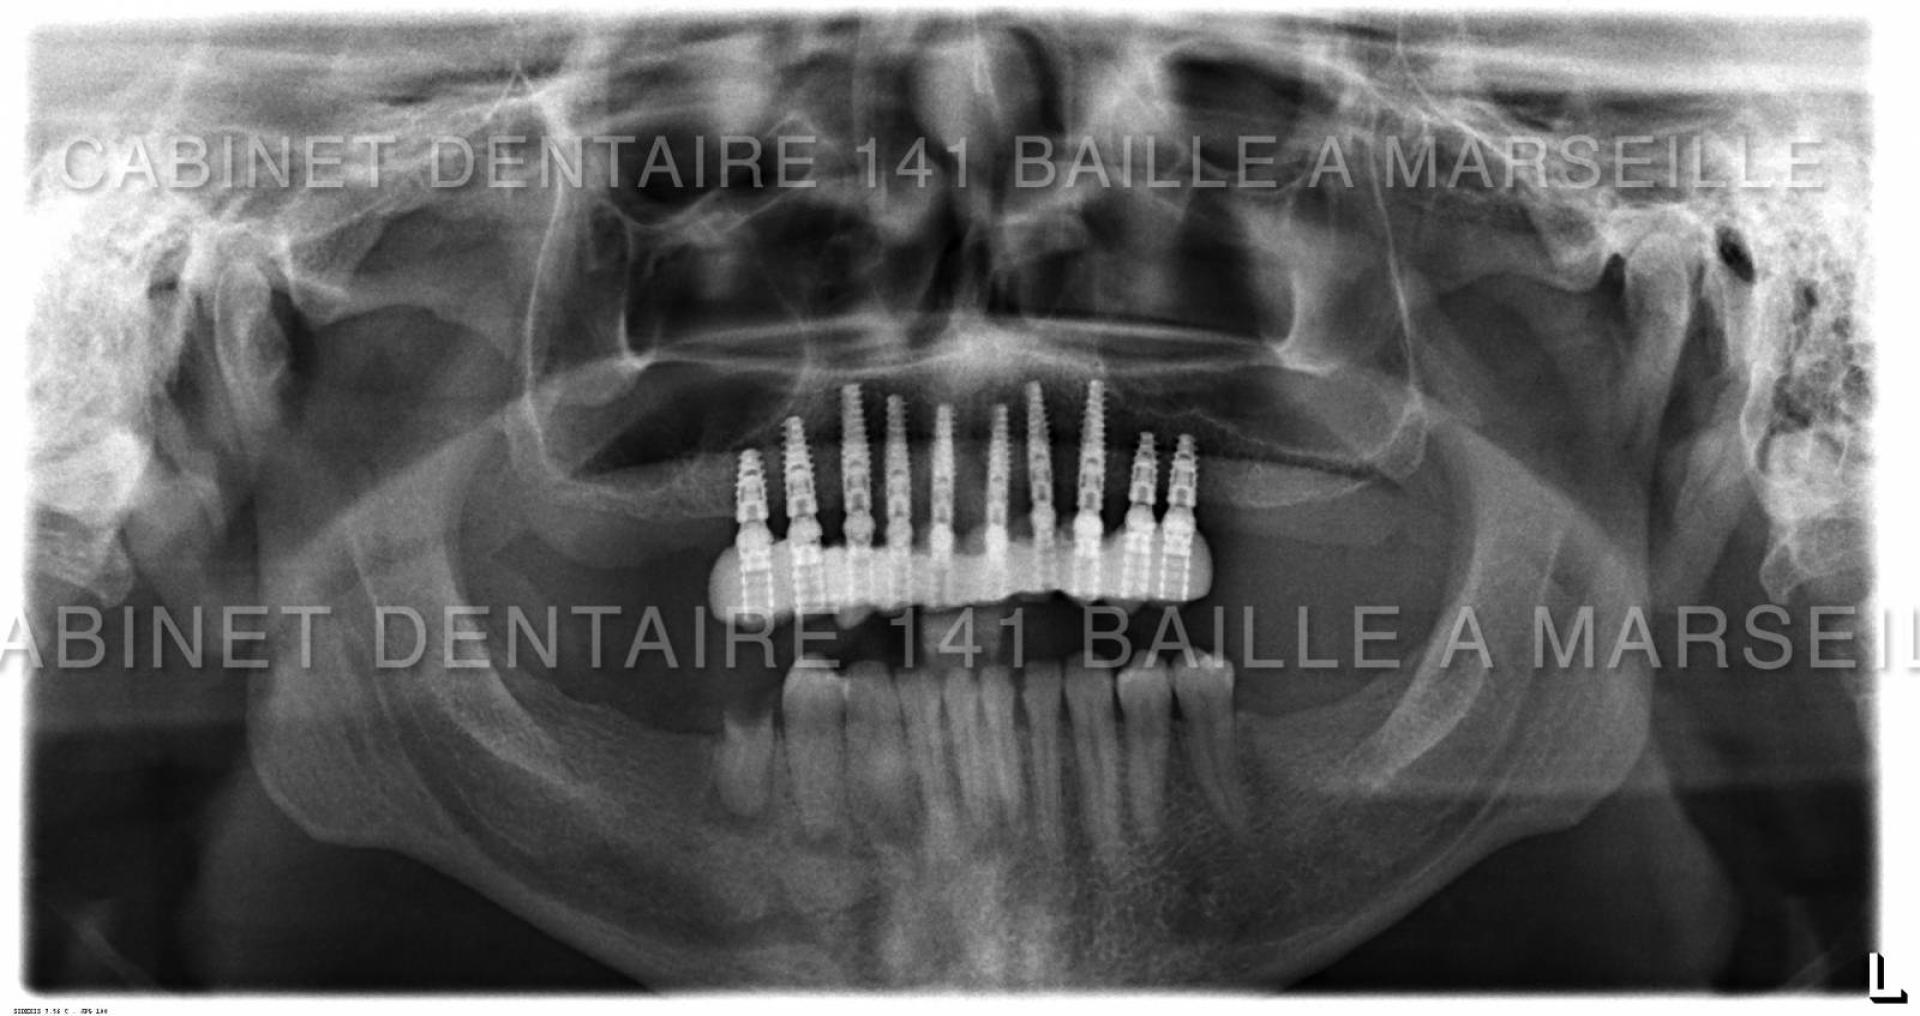

Nous sommes en mesure d'assurer la prise en charge de vos patients dans notre structure qui englobe la phase chirurgicale traitée naturellement en bloc opératoire stérile ,et sytème de traçabilité chirugicale aux normes hospitalières (Cycles prions à fractionnement de vide) ,pour tous les cas complexes intégrant implantations totales avec mise en charge immédiate.

Notre laboratoire intégré nous délivrera une prothèse immédiate qui permettra à votre patient de na pas avoir de gêne au niveau de sa vie sociale.

En général nous commençons à opérer le matin vers 9 h et la patient rentre chez lui vers 13h équipé d'une prothèse immédiate implanto- portée.